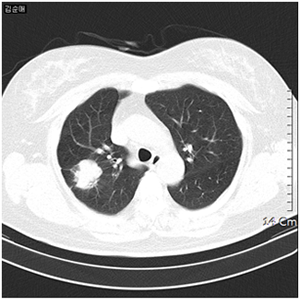

폐암 환자의 흉부 CT